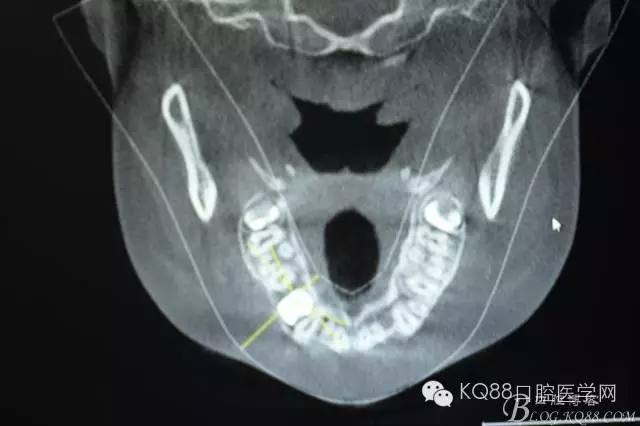

圖5.水平剖面觀:14牙冠緊鄰15與13牙根之間,要求分牙一定要小心謹(jǐn)慎